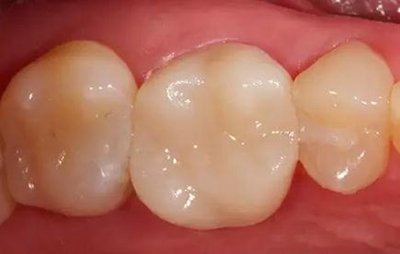

最終修復冠

拋光后的修復冠。由VITA SUPRINITY材料制作, 選擇1M2-HT。